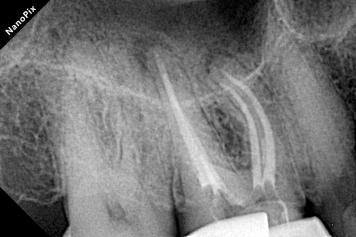

Patient Info:A 65-year-old patient presented with biting pain and a buccal sinus tract (fistula) on the right maxillary first molar (Tooth 16).

Radiograph:Radiolucency at the apex of the mesiobuccal (MB) root; severe calcification in the pulp chamber and the coronal third of the canals.

Locating the Hidden Anatomy: Due to heavy calcification, ultrasonic tips were used.

Successfully located the MB1 and the extremely narrow MB2 canal under magnification.